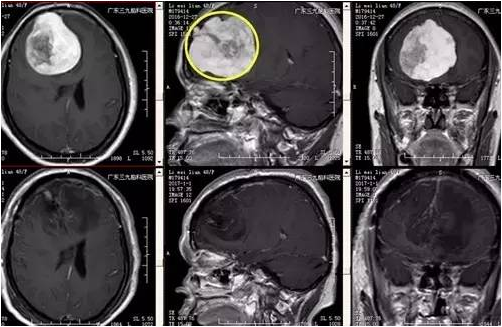

李女士,48岁,3年前开始出现间断头痛,能自行缓解,近20天头痛加重无法忍受,遂来我院门诊就诊,CT提示右侧额部类圆形稍低密度影,入院后完善检查,MR示右侧额部镰窦旁旁巨大脑膜瘤,病灶大小约7.0cm*5.9cm*6.4cm,CTA提示肿瘤周围血管包绕,血供丰富。患者手术由神经外一科主任张良主刀完成,行全麻下右侧额部镰窦旁巨大脑膜瘤切除术,术后患者症状消失,目前恢复良好出院。

脑膜瘤是颅内最常见的良性肿瘤,一般将最大径大于7.0cm的脑膜瘤称为巨大脑膜瘤。手术是治疗颅内巨大脑膜瘤的最佳方法,应争取做根治性全切除手术,以减少复发。巨大脑膜瘤血供丰富,常与颅神经、大动脉、海绵窦等粘连,或侵犯静脉窦等,手术难度大,风险高,致死致残率高。本例患者病变与大脑镰窦关系稍密切,病灶大小约7.0cm*5.9cm*6.4cm,其内示多发小血管穿行;病灶局部突入额部板障内,病变范围颅骨变薄,板障血供丰富,术中去除颅骨时出血较多。术中应用显微操作,仔细分离肿瘤周围的大脑前动脉,保护嗅神经,尽量减少了脑组织不必要的牵拉。由于肿瘤浸润矢状窦,手术时切除累及的矢状窦和大脑镰,做到肿瘤一级切除。术后患者一般情况良好,密切监测颅内压力变化及病情变化,术后有一过性发热,未有明确神经功能障碍及并发症,恢复良好出院。